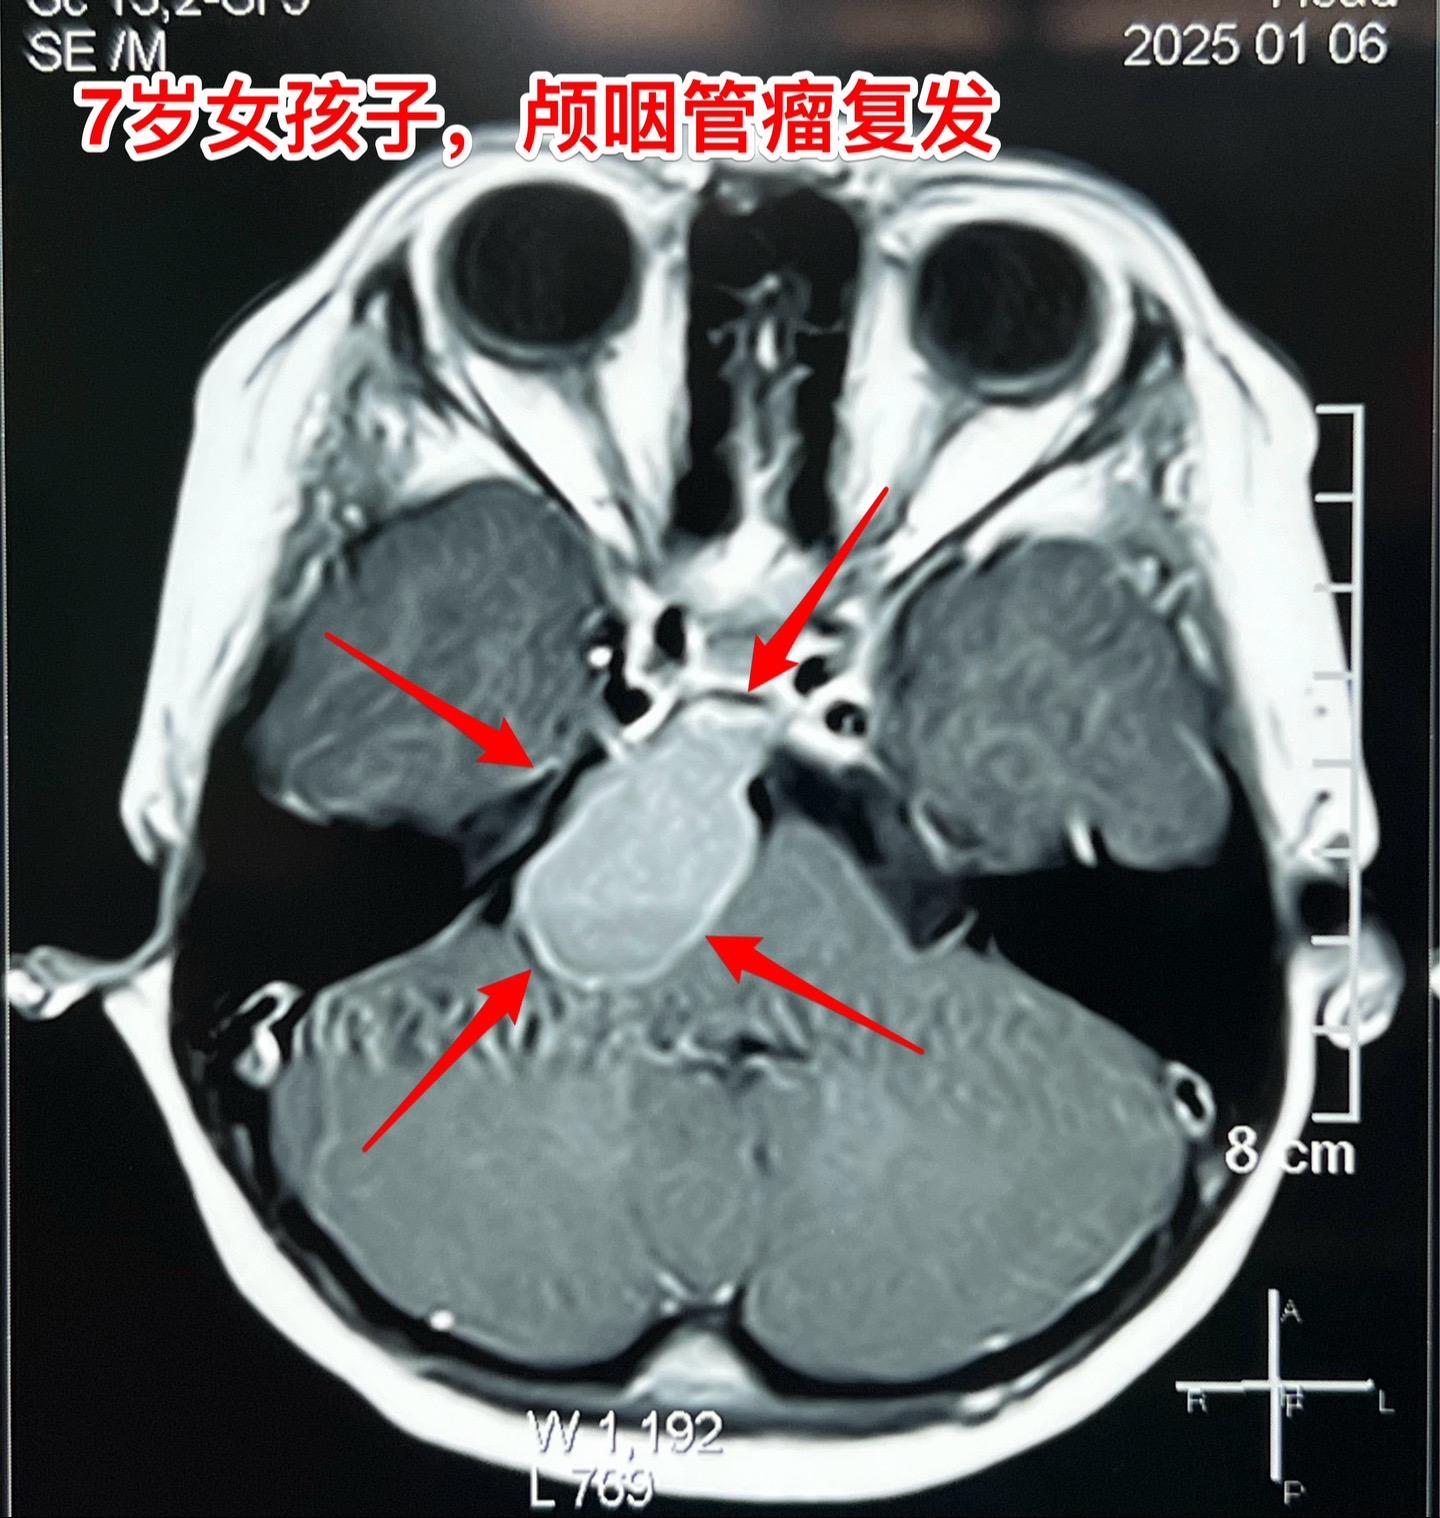

颅咽管瘤复发,看起来是一个瘤其实有三个。7岁女孩子,颅咽管瘤复发。从CT和磁共振来看,是一个大的囊性肿瘤,体积很大了,肿瘤向后颅窝生长,手术切除的难度还是比较大的。 2025年1月10日作手术过程中发现的情况比预想的还要复杂得多。除了这个大的囊性肿瘤之外还发现了两个孤立肿瘤。 这样的情况在我们科并不罕见,经常发现复发的颅咽管瘤病人脑部不止是一个瘤,有的时候有超过10个孤立的肿瘤。这种情况就要考验医生的技术和意志力了。当然,在我们科,总是争取把看见的瘤完全切除。